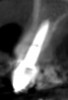

In this first case, OD burs were used at a site requiring maxillary sinus augmentation, an area that is frequently associated with low-density bone. A 60-year-old female patient presented with missing posterior teeth in the right maxillary quadrant. Clinical and cone-beam computed tomography (CBCT) evaluation revealed a partially pneumatized maxillary right sinus with residual bone height of 5 mm (Figure 1 and Figure 2). A lateral sinus augmentation procedure was planned as a result of the minimal residual bone height present and would include simultaneous placement of two implants (one-stage).

Fig 2. CBCT image demonstrating extensive bone loss in right maxillary quadrant with loss of residual bone height in the sinus.

Figure 2